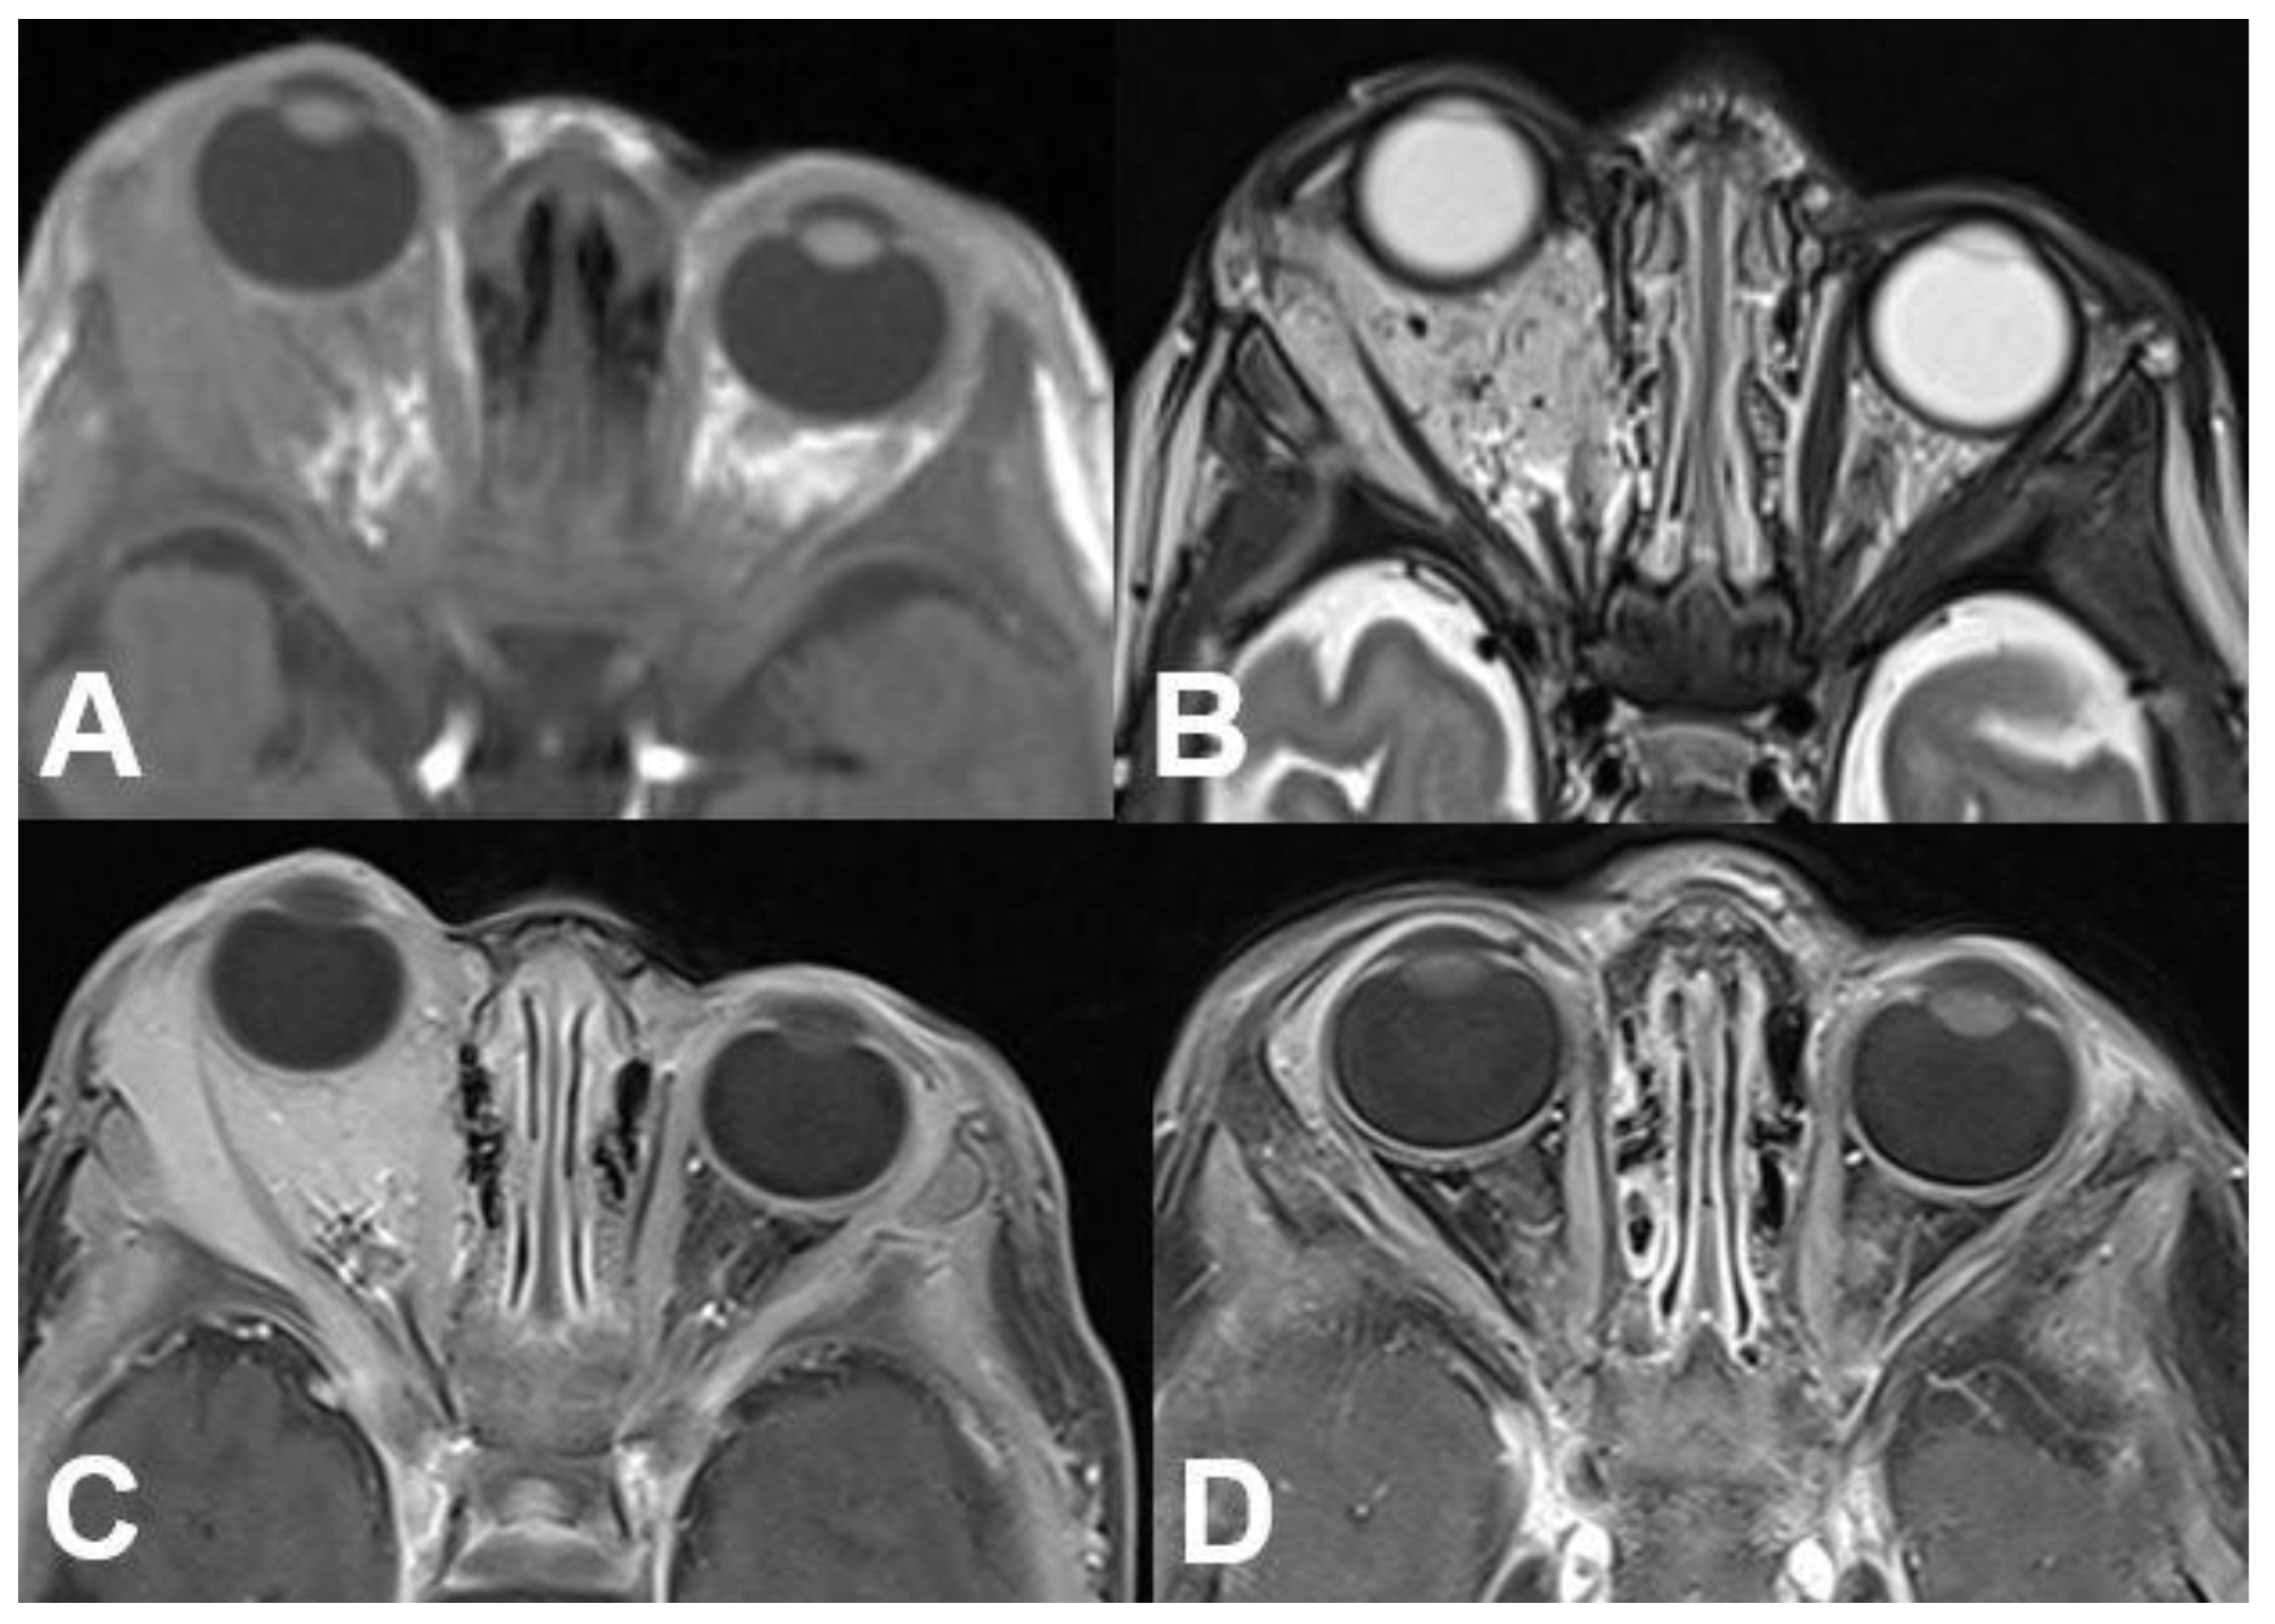

3.4. N. opticus

3.4.1. Optic Nerve Glioma

3.4.2. Optic Nerve Sheath Meningioma

3.5. Peripheral Nerve Sheath

3.5.1. Schwannoma

3.5.2. Neurofibroma